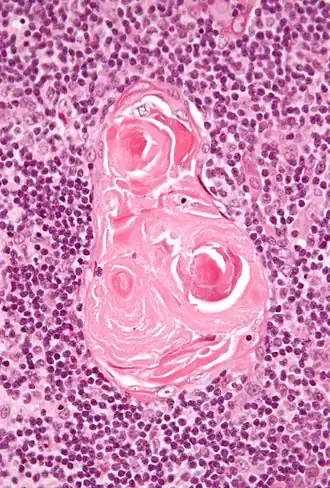

Es producida por células situadas en los corpúsculos tímicos o corpúsculos de Hassall ubicados en la médula del timo.[1]